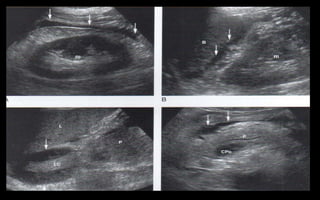

HIGADO

 Peso de 1500 gramos

 Órgano más grande del cuerpo humano

 Se de evaluar con ayuno y vejiga distendida

 Evaluarse en proyecciones sagital, transversa,

coronal y oblicua subcostal.

 Se divide en tres lóbulos: Derecho, izquierdo y

lóbulo caudado

 El lóbulo derecho está separado del izquierdo

por la fisura lobar principal, LD se divide en los

segmentos anterior y posterior

 Lóbulo izquierdo se divide en los segmentos

medial y lateral.

 El lóbulo caudado esta situado en la cara

posterior del hígado y tiene como borde

posterior la vena cava inferior y como borde

anterior la fisura para el ligamento venoso.

 El borde superior se dispone

alrededor del nivel del 5to espacio

intercostal en la línea media clavicular

 El borde inferior se extiende hasta

ligeramente por debajo del borde

costal.

 Hígado se mide en el eje longitudinal,

línea clavicular media, el lóbulo

derecho.

 13 cm a 15,5 cm (130 a 155 mm).

 La medida, va a depender de la edad,

sexo, talla, peso, superficie corporal.

ANATOMIA DE

COUINAUD

 Se utiliza para localizar

una lesión hepática

 Se basa en segmentos

portales y tiene

importancia funcional y

patológica.

 Cada segmento tiene un

aporte sanguíneo

(arterial, venoso portal y

venoso hepático),

linfáticos y drenaje biliar

propios

 Existen ocho segmentos

 Las venas hepáticas,

derecha, media e

izquierda dividen al

hígado longitudinalmente

en cuatro secciones